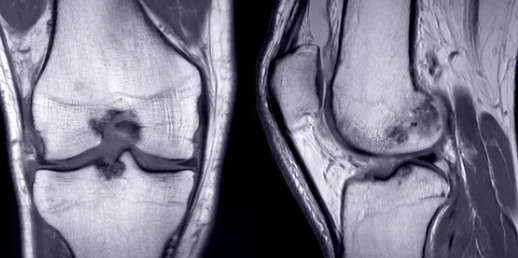

3. 무릎 관절삼출 진단 방법

✅ 병원에서 진행하는 주요 진단 검사

검사 방법 설명

| X-ray 검사 | 무릎 관절의 골절, 뼈의 이상 여부 확인 |

| MRI 검사 | 연골 손상, 인대 파열, 관절 내 염증 확인 |

| 초음파 검사 | 무릎 내부의 염증 및 관절액 증가 여부 평가 |

| 혈액 검사 | 류마티스 관절염, 통풍 등의 염증 수치 확인 |

| 관절액 검사 (관절천자) | 주사기로 관절액을 채취하여 감염 여부, 염증 원인 분석 |

- 무릎 관절염과 연골 손상 여부를 구별하기 위해 MRI 검사가 효과적입니다.

- 류마티스 관절염이나 감염성 관절염이 의심될 경우, 혈액 검사 및 관절액 검사가 필수적입니다.